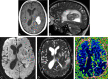

CNS lymphoma consists of 2 major subtypes: secondary CNS involvement by systemic lymphoma and PCNSL. Contrast-enhanced MR imaging is the method of choice for detecting CNS lymphoma. In leptomeningeal CNS lymphoma, representing two-thirds of secondary CNS lymphomas, imaging typically shows leptomeningeal, subependymal, dural, or cranial nerve enhancement. Single or multiple periventricular and/or superficial contrast-enhancing lesions are characteristic of parenchymal CNS lymphoma, representing one-third of secondary CNS lymphomas and almost 100% of PCNSLs. New CT and MR imaging techniques and metabolic imaging have demonstrated characteristic findings in CNS lymphoma, aiding in its differentiation from other CNS lesions. Advanced imaging techniques may, in the future, substantially improve the diagnostic accuracy of imaging, ultimately facilitating a noninvasive method of diagnosis. Furthermore, these imaging techniques may play a pivotal role in planning targeted therapies, prognostication, and monitoring treatment response.